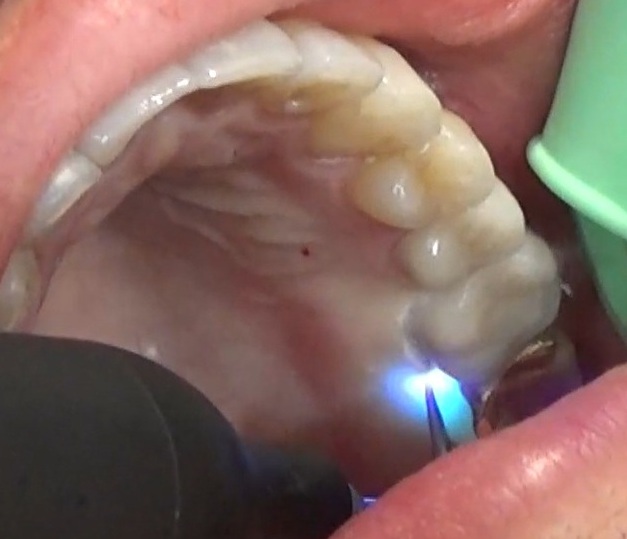

(施術風景)

深い歯周ポケットに青いレーザー光と過酸化水素水を照射し、患部を殺菌します。

(実施前)

施術前のレントゲンと口腔内写真です。

深い歯周ポケットに青いレーザー光と過酸化水素水を照射し、患部を殺菌しています。